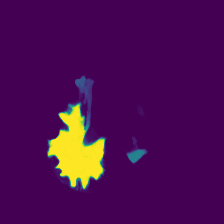

Diffusion models have shown impressive performance for generative modelling of images. In this paper, we present a novel semantic segmentation method based on diffusion models. By modifying the training and sampling scheme, we show that diffusion models can perform lesion segmentation of medical images. To generate an image specific segmentation, we train the model on the ground truth segmentation, and use the image as a prior during training and in every step during the sampling process. With the given stochastic sampling process, we can generate a distribution of segmentation masks. This property allows us to compute pixel-wise uncertainty maps of the segmentation, and allows an implicit ensemble of segmentations that increases the segmentation performance. We evaluate our method on the BRATS2020 dataset for brain tumor segmentation. Compared to state-of-the-art segmentation models, our approach yields good segmentation results and, additionally, detailed uncertainty maps.